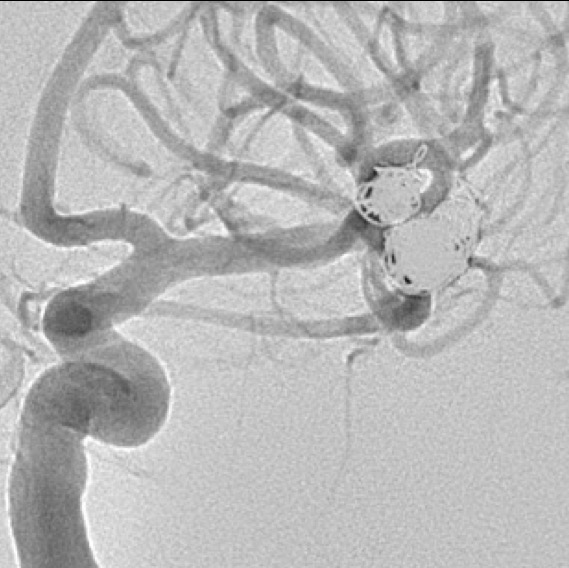

Fig. 4. Angiografia digital 3D: Aneurisma sacular pequeño bilobulado, con pseudoaneurisma asociado, responsable del sangrado.

Fig. 5. Angiografia digital con substracción: Aneurisma sacular pequeño bilobulado, con pseudoaneurisma asociado, responsable del sangrado, a nivel de la bifurcación de la arteria cerebral media izquierda.